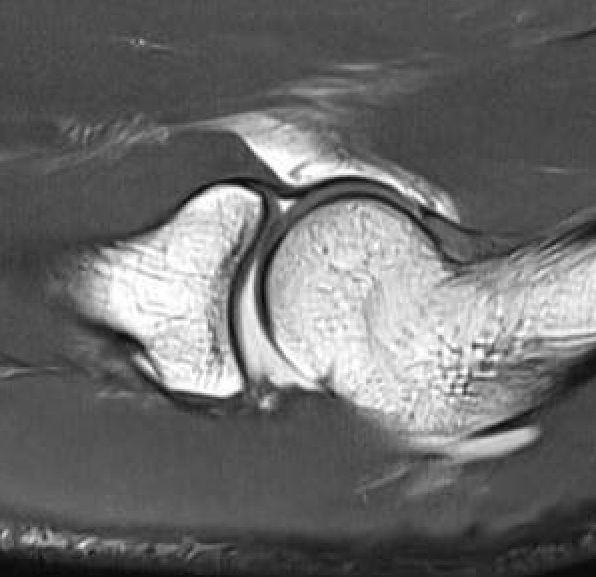

MRI

Normal

PRLI

Subtle instability of the radiocapitellar joint